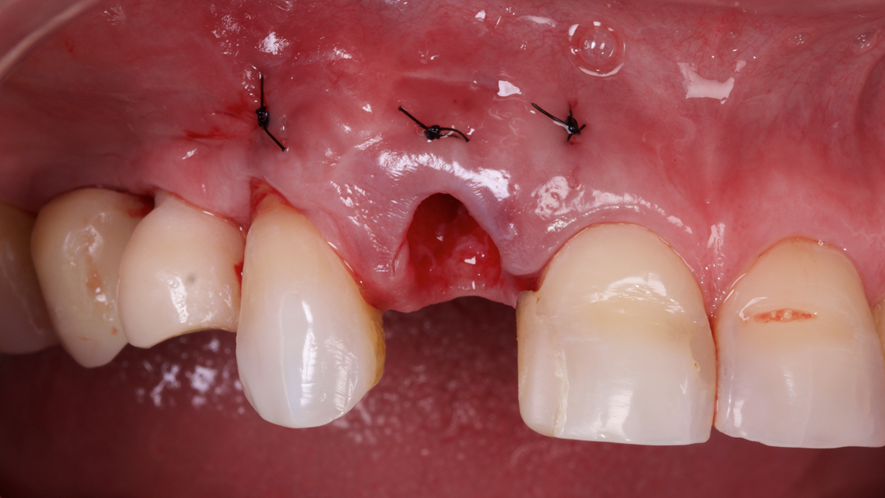

Este trabalho tem como objetivo relatar um caso clínico de exodontia minimamente invasiva de um incisivo lateral superior com fratura radicular, realizando implante imediato em alvéolo pós-extração, enxerto de tecido conjuntivo subepitelial e osso bovino liofilizado para preenchimento de GAP, prontamente à instalação de pilar reto e provisório imediato.